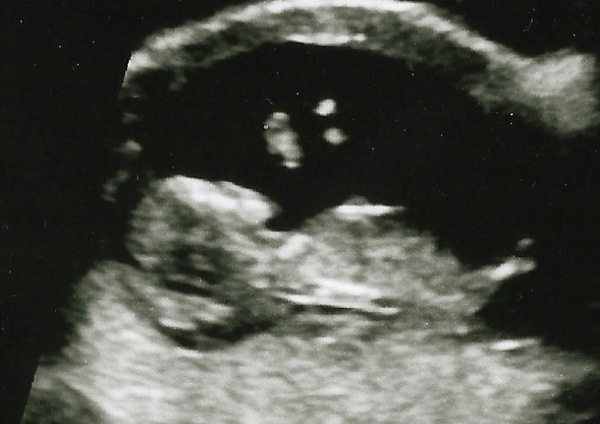

Daisy glad your scan went well.